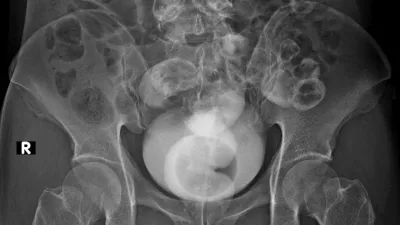

Rentgenska (simbolična) slika / Foto: Istock

Rentgenska slika / Foto: Istock